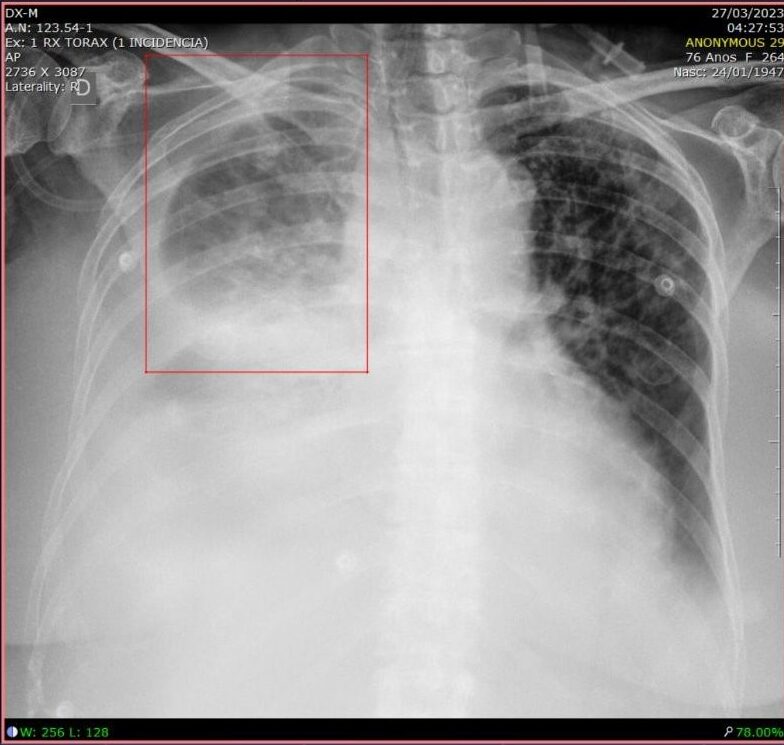

Raio-X de pulmão com Inteligência Artificial

A pneumonia é uma infecção pulmonar responsável por mais de 600 mil internações por ano no Sistema Único de Saúde (SUS) brasileiro.

O diagnóstico de pneumonia em uma radiografia de tórax envolve especialistas treinados e cruzamento de informações de histórico clínico, sinais vitais e exames laboratoriais.

Para ajudar nesse desafio, algoritmos de machine learning podem detectar manchas de opacidade pulmonar (derrame pleural, cardiomegalia, edema pulmonar agudo, nódulos pulmonares) e sinalizá-las em caixas para avaliação médica, especificando a localização e o tamanho de qualquer infecção detectada.

Isso traz produtividade para os médicos sobre as decisões de tratamento (pneumonia leve versus pneumonia severa, por exemplo) e também retroalimenta o sistema à medida que os médicos validam ou descartam o achado clínico sinalizado pelo computador.